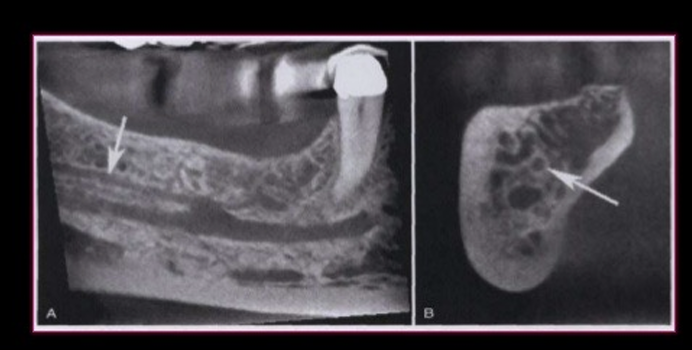

bifid mandibular canal

a) cone beam scan

b) cross section